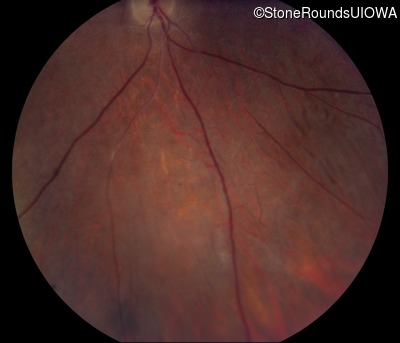

Fundus Photography - Right - 10/200

Exemplar

Fundus Photography - Left - 10/100 -2